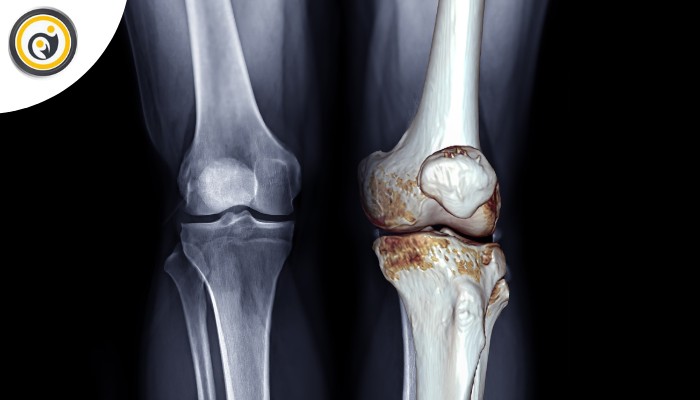

رادیوگرافی ساده (X-ray)

برای بررسی آرتروز، فاصله مفصلی، وجود خار استخوانی، شکستگیهای پنهان و تغییرات ساختاری اولیه زانو کاربرد دارد.

برای مشاهده دقیق مینیسکها، رباطها، تاندونها، غضروف مفصلی و التهاب بافتهای نرم استفاده میشود. اگر درد با معاینه یا X-ray بهخوبی مشخص نشود MRI بهترین گزینه است.

سی تی اسکن

برای بررسی دقیقتر استخوان، شکستگیهای پنهان یا ارزیابی شکل استخوانی زانو و محور آن در موارد خاص انجام میشود.